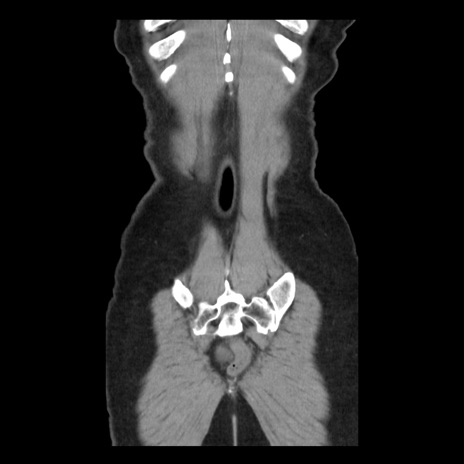

矢状断像

【症例】 50歳代女性

【主訴】 腹痛

【現病歴】前日生レバーを食べた。今朝に排便あり。 昼前に突然発症の腹痛を生じ、当院救急外来を受診した。

【既往歴】 子宮筋腫にてで子宮全摘後

【身体所見】 意識清明、腹部:平坦、軟、下腹部やや左を中心に圧痛・反跳痛あり、筋性防御あり

【データ】WBC 7800、CRP 0.07